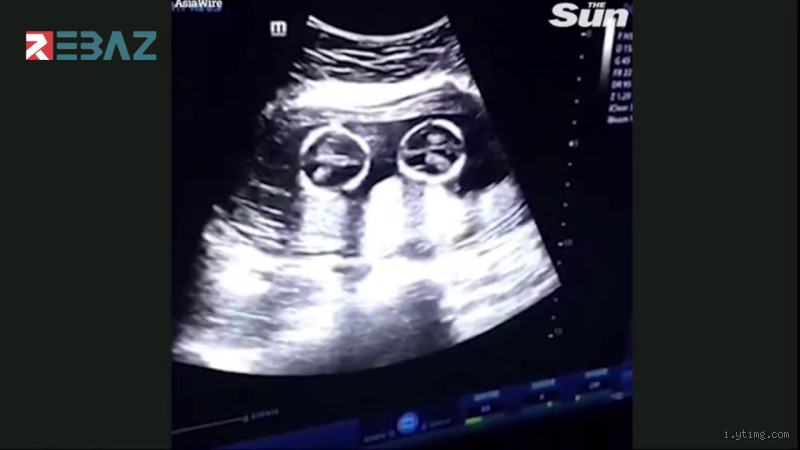

1. التصوير بالأمواج فوق الصوتية (السونار)

الطريقة الأكثر دقة لمعرفة إذا كنتِ حاملاً بتوأم هي عن طريق السونار. عادةً ما يتم الكشف عن الحمل بتوأم خلال الأشهر الأولى باستخدام هذه التقنية. يمكن للطبيب أن يرى جميع الأجنة في الرحم ويؤكد ما إذا كان هناك حمل بتوأم أم لا.

إذا كنتِ تشعرين بالقلق أو الفضول، يمكنكِ زيارة طبيبكِ بمجرد أن يكون لديكِ اختبار حمل إيجابي. قد يطلب منكِ الطبيب إجراء فحص سونار مبكر لتحديد ما إذا كان هناك توأمان.